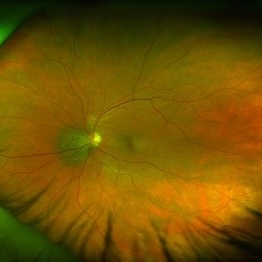

Small, Peripapillary Choroidal Melanoma of the Left Eye - Standard Color

Small, Peripapillary Choroidal Melanoma of the Left Eye - Standard Color

Feb 13 2020 by Michael Seider, MD

Small, peripapillary choroidal melanoma of the left eye. Note the diffuse borders, clumped overlying orange pigment (lipofuscin) and lack of drusen. The standard fundus photograph reveals the true color of the lesion. The wide-field Optos photograph shows the lesion as being more green than the true color, although the lipofuscin remains prominently orange. Wide-field fundus autofluoresence shows a bright signal corresponding to the orange pigment and also superior and inferior to the optic nerve, likely from previous exposure to subretinal fluid. Optical coherence tomography confirms the subretinal fluid seen on examination. B-Scan ultrasonography shows a very low-lying choroidal lesion adjacent to the optic nerve.